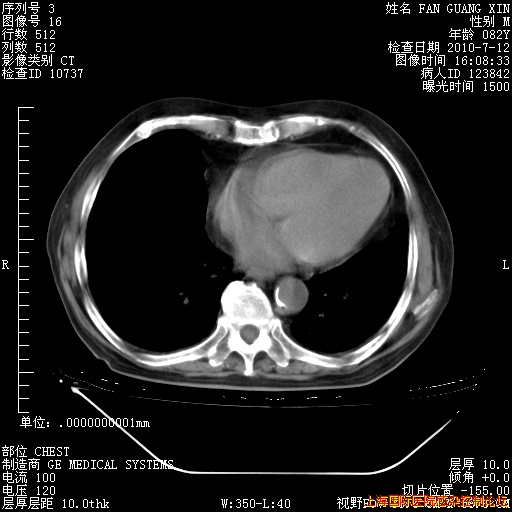

6月12日纵膈窗

今天CT

整整相隔30天的肺部CT好像有所好转啊。甲强龙减量第3天,需要观察体温。

海管,自昨日你和我通完话后,不知您岳父消化道症状有无缓解?体温怎样?阅读7.12日胸部ct,个人认为目前激素治疗是有效的,甲强龙减量是适宜的。因在抗痨治疗,需密切观察肝功、肾功能和血常规。不过,老年、长期住院和大量使用激素,很担心菌群失调发生